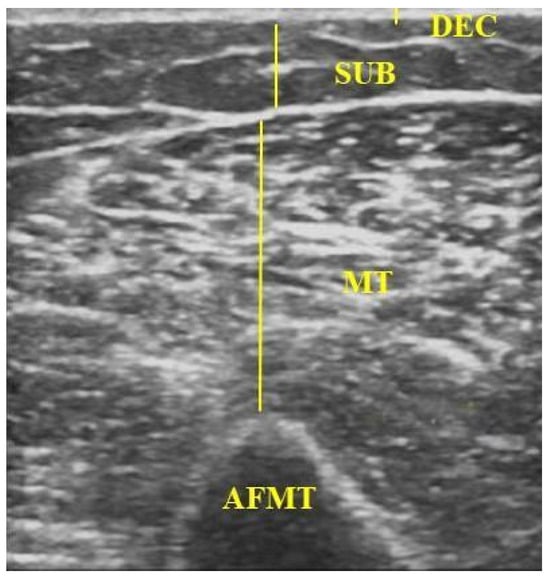

| DEC | dermal–epidermal complex |

| SUB | subcutaneous tissue |

| MT | muscle thickness |

| AFMT | arm flexor muscle thickness |